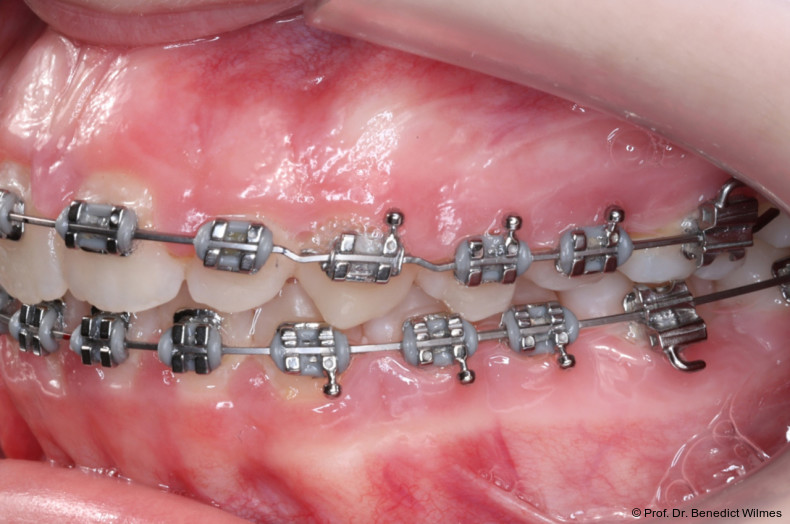

Nach erfolgreicher Expansion und Molaren­intrusion wurde eine Multibracket-Therapie zur Ausformung und Koordination der Zahnbögen durchgeführt (Abb. 8a–f). Nach Abschluss der aktiven Behandlungsphase wurden die Apparaturen entfernt und festsitzende Retainer im Ober- und Unterkiefer eingesetzt (Abb. 9a–k).